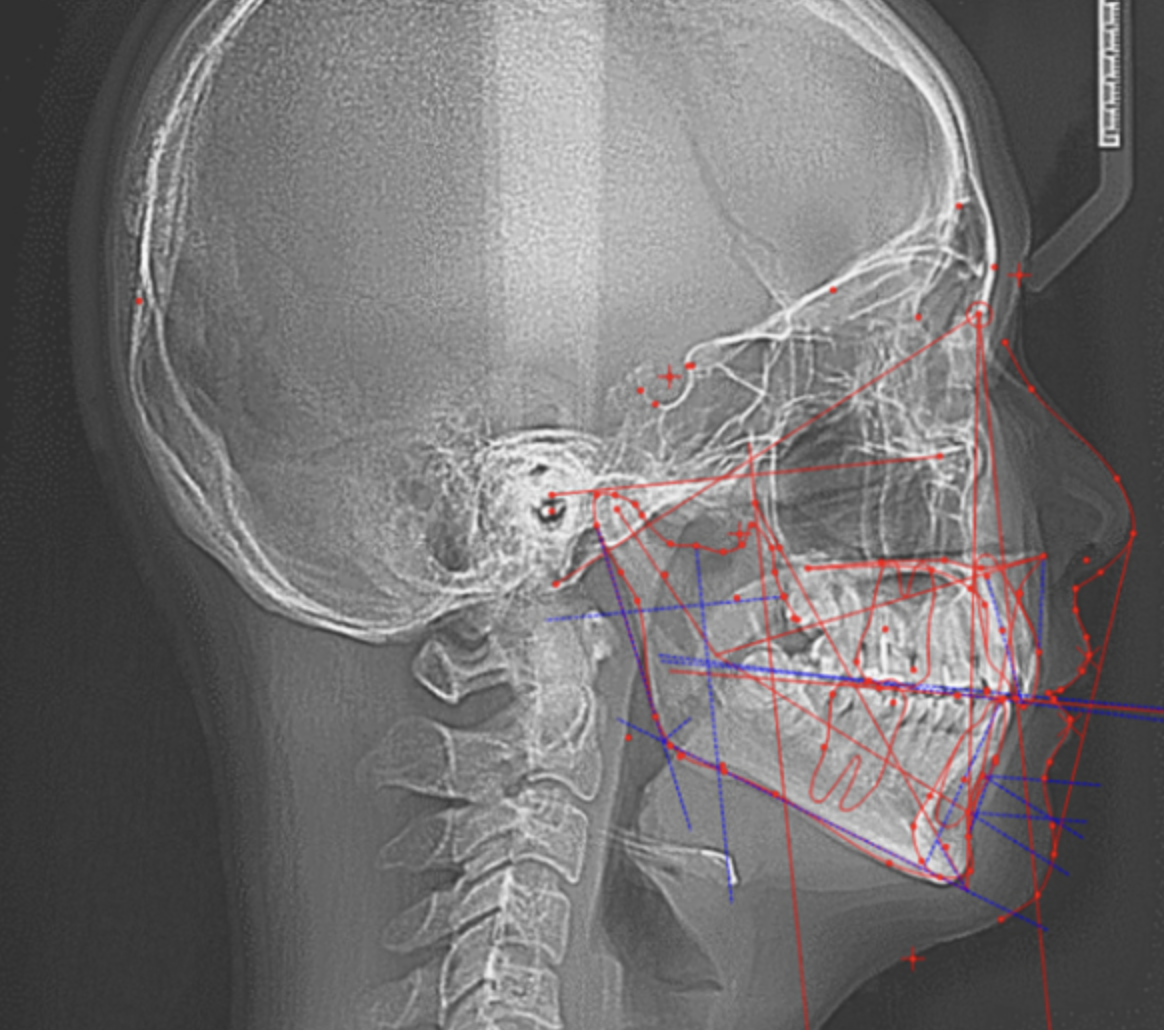

20代女性:AngleⅠ級叢生の症例

治療前

治療前